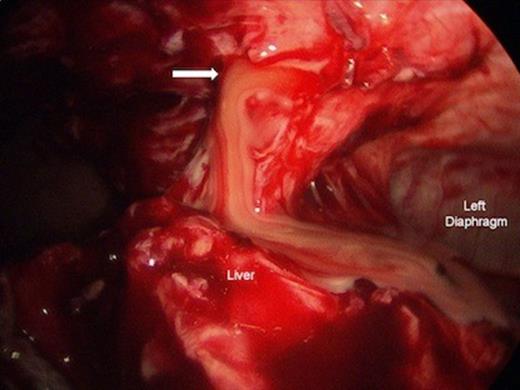

A 54-year-old female with a history significant for alcohol abuse, surgical correction of annular pancreas 20 years ago and chronic pancreatitis presented to a rural emergency department with a 1-week history of worsening severe epigastric pain, nausea and vomiting. She was in baseline health until 2 months prior when she first noticed episodic epigastric pain that was stabbing in nature. The patient was transferred to our institution for surgical evaluation based on an external department CT raising concern of possible diaphragmatic herniation versus fluid collection. Re-scan of the abdomen confirmed a fluid collection of 8-10 cm in the extra-peritoneal space of the intra-abdominal wall, extending superiorly to the anterior mediastinum. Subsequent laparoscopy revealed dense omental adhesions encapsulating an abscess cavity, which tracked into the inferior mediastinum. Purulent material was evacuated, fluid was sampled for bacterial culture and a Blake drain was placed. There was no evidence of existing mesh, intestinal fistula or enterotomy. The precise etiology of the abscess remains unclear. The patient was afebrile without leukocytosis throughout the hospital course and was discharged with clinic follow-up after 3 days of post-operative evaluation. At the one-month post-operative clinic visit, symptoms had resolved.

Laparoscopic drainage of anterior inferior mediastinal abscess. Left diaphragm and liver are shown. Arrow = Mediastinotomy.